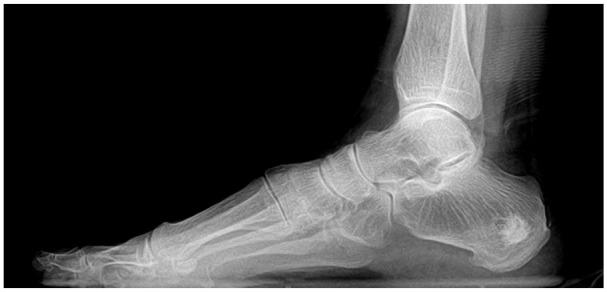

Comparison of Calcaneal Subchondral Injection of Calcium Phosphate and Plantar Fasciotomy vs Plantar Fasciotomy Alone for Refractory Infracalcaneal Heel Pain.

Treatment of chronic refractory heel pain has evolved to consider calcaneal structural fatigue as a component of the symptom profile. While concomitant calcium phosphate injection has become a method of addressing the accompanying calcaneal bone marrow edema (BME) frequently seen in this population, there is no literature supporting its use compared to traditional fasciotomy.

Consecutive patients with symptoms of refractory infracalcaneal heel pain and calcaneal BME were treated in our practice by either surgical fasciotomy (n = 33) or fasciotomy plus calcium phosphate injection (n = 31) between 2014 and 2019. Outcomes were retrospectively assessed via Foot and Ankle Outcome Scores (FAOS), return to activity, and complication rate.

Sixty-four patients (64 feet) were included with a mean age of 50.3 ± 12.9 years and mean follow-up of 23.2 ± 22.3 months. No differences were observed between groups preoperatively. Significant improvements in 4 of 5 FAOS subscales were observed postoperatively in both groups ( < .05 for all, paired test). However, patients undergoing concomitant calcium phosphate injection reported significantly better scores for both activities of daily living (ADL; mean difference +10.2; 95% confidence interval [CI] 0.07-20.2) and foot-specific QOL (mean difference +21.9, 95% CI 7.0-36.6) at final follow-up compared with those undergoing plantar fasciotomy alone. All patients returned to their desired level of activity, and the frequency of complications did not differ between groups ( > .05, Fisher exact test).

In patients presenting with recalcitrant infracalcaneal heel pain accompanied by calcaneal BME, calcium phosphate injection into the calcaneus, when combined with plantar fasciotomy, was safe and more effective than traditional plantar fasciotomy alone.